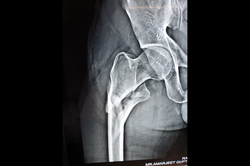

Intertrochanteric Fracture